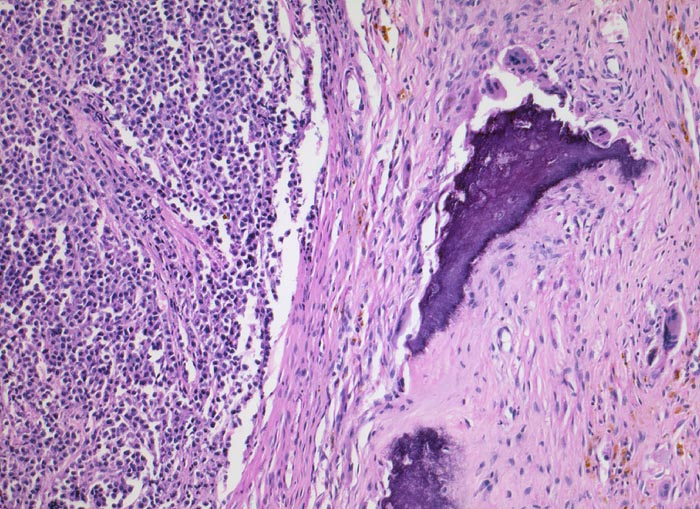

Plasmazellmyelom

Knochenmark, Wirbelkörper

Homogenes Tumorgewebe links im Bild ohne erkennbare Knochenmarksanteile. Ein Knochenbälkchen am Rande des Präparates wird von Osteoklasten resorbiert. Im Bindegewebe finden sich Makrophagen mit gelbbraunen Hämosiderineinlagerungen im Zytoplasma als Folge von Tumornekrosen und Blutungen.

Notfalleinweisung wegen umschriebenen Thoraxschmerzen ohne adäquates Trauma. Im Röntgenbild Nachweis multipler Frakturen der Wirbelsäule und der Rippen bei grobsträhniger Osteoporose. In der Serumelektrophorese Nachweis einer Paraproteinämie.